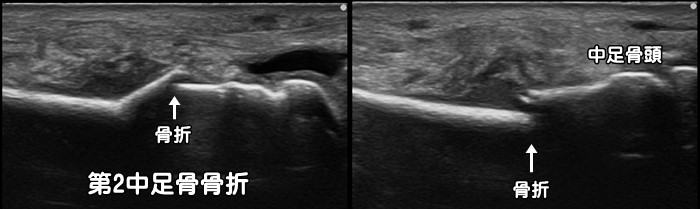

中足骨骨折

足の甲に掃除機を落とし負傷。病院で2回レントゲンを撮るも骨折は確認できず。随分と腫れが強いので当院を受診。エコーではしっかりと骨折と炎症反応が確認できます。足の骨はレントゲンでは複数の骨が重なり合うため骨折を確認できない事が多々あります。